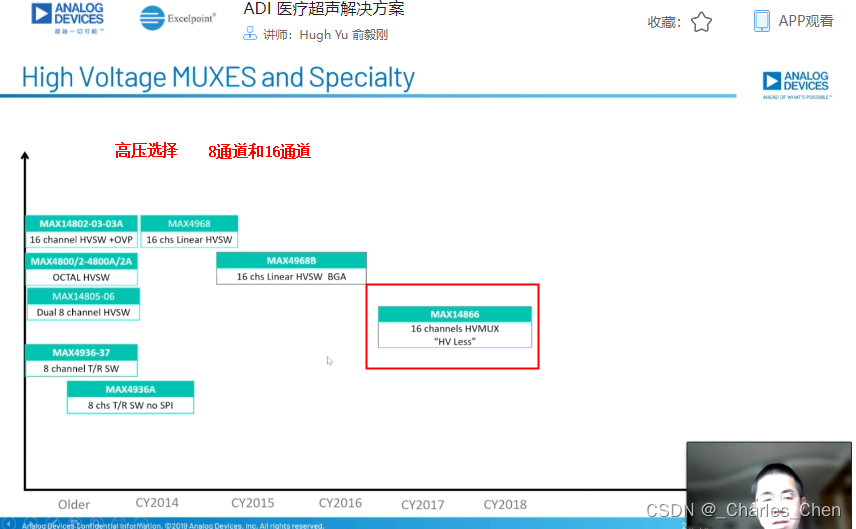

高压复用开关

典型的相控阵超声系统配备了32至256个发射器和接收器。多数情况下,系统配备的发射器和接收器的数量少于传感器单元的数量。这些情况下,需要在传感器或系统中安装高压开关,用于信号复用,开关连接在特定的传感器单元和发送器/接收器(Tx/Rx)对之间。由此,系统能够在所提供的传感器阵列中动态改变有效的传感器孔径。

成像系统对高压开关的要求主要包括几个方面:必须能够承受电压摆幅高达200VP-P且峰值电流高达2A的发射脉冲;开关必须能够迅速切换,以快速调整有效孔径、满足图像帧率的要求;最后,这些开关还必须具有极小的电荷注入,从而避免杂散传输以及相关的虚假图像。